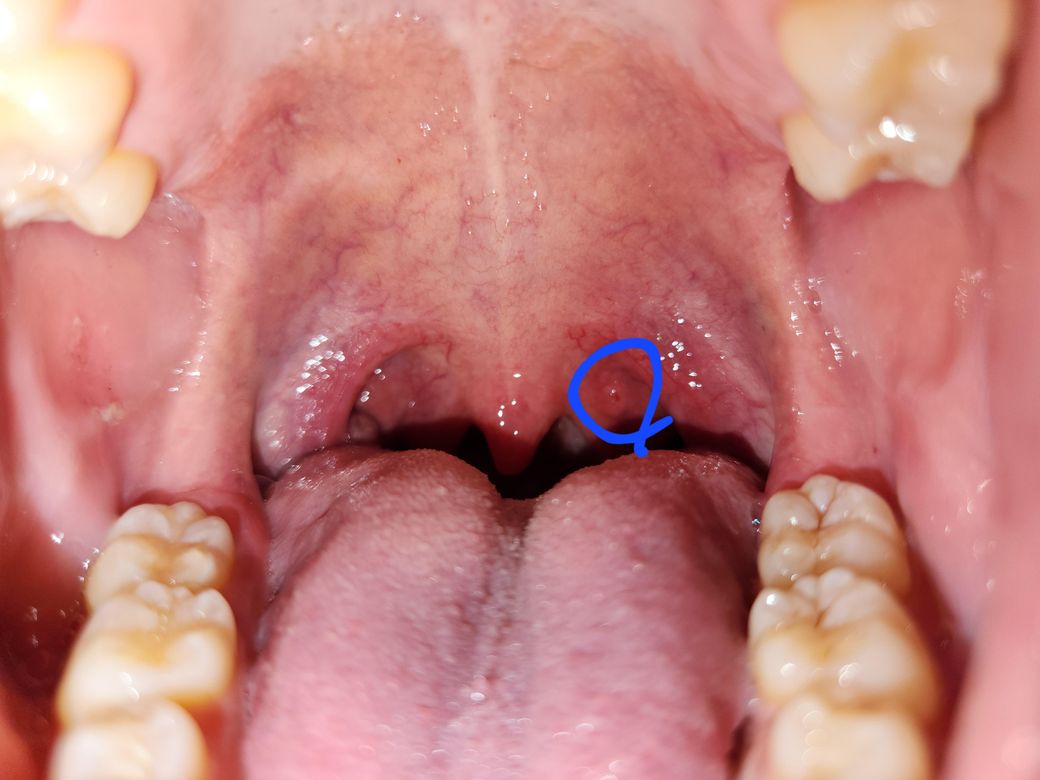

왼쪽 목구멍 윗쪽에 뭐가 났는데 이게 뭘까요...?

이따금씩 구내에 생기는 수포같은건줄 알고 손 씻고 터트리려고 했지만 터지진 않고 생각보다 단단한? 느낌이더라고요.

검색해보니 비인두암이라는 무서운 암일까 걱정이 많이 됩니다... 당연히 병원에 가고 싶지만 현재 미국 출장 중으로 4주 후 귀국 예정입니다 ㅜ

• 2번 째 사진

올려주신 사진으로 미루어 악성 병변보다는 양성 질환의 가능성이 더 생각되나 귀국 후 이비인후과 진료를 받기 바랍니다.

음주, 흡연, 카페인, 자극적 음식의 섭취와 과도한 목 사용을 피할 것을 권합니다.